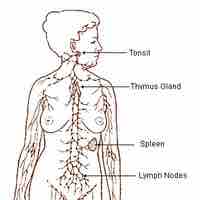

The immune system includes primary lymphoid organs, secondary lymphatic tissues and various cells in the innate and adaptive immune systems.

The lymphatic system houses large populations of immune cells which are released upon detection of a pathogen.